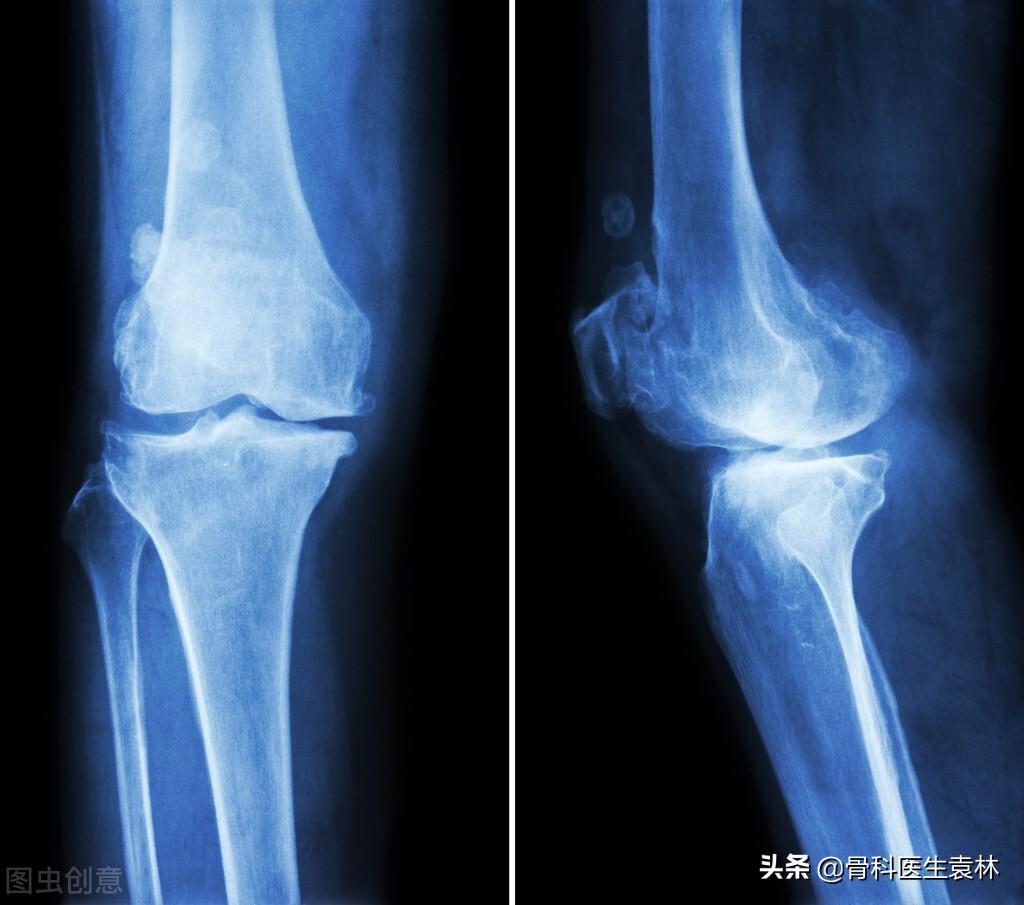

支气管扩张

支气管扩张是一种支气管管壁结构破坏性疾病,正常情况下,支气管是一个带有弹性,拥有一定管径的能够维持正常呼吸通气的结构,当管壁结构受到破坏时,气管会受到被动的牵拉而扩张,管壁的血管由于弹性较小,容易被撕扯呈血管瘤改变,一旦胸腔内血流压力增大可能冲破血管瘤变薄的管壁而导致大咯血,少量渗血时则呈现为痰中带血。